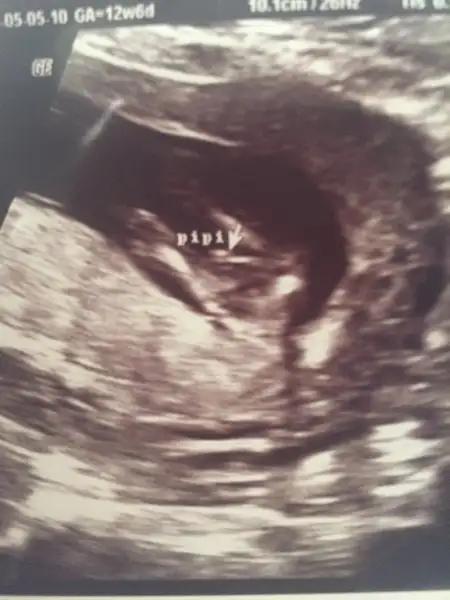

valla bana 10+2 de kız olabilir dedi.12+6 da kesin erkek dedi Can'ım hatta pipi nin çıktısını bile verdi.

Eklentiler

• image.webp

image.webp

13,2 KB · Görüntüleme: 88